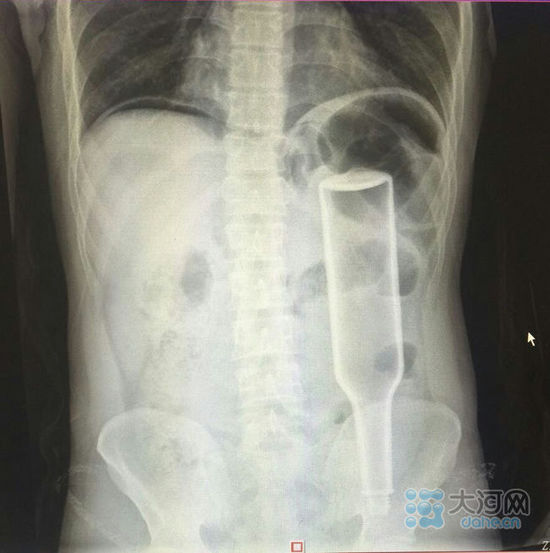

看這片子,花露水瓶子已經(jīng)很“深入”了。

大河網(wǎng)訊在鄭州務(wù)工的外地男子王某,下班到家后閑著沒事兒干,于是將一個(gè)長18厘米的花露水瓶子塞進(jìn)了自己的肛門,不過因?yàn)橛昧^猛,快感沒來,瓶子卻把直腸給戳破了,疼得受不了了,王某羞答答地來到鄭州人民醫(yī)院就診,醫(yī)生給他做了手術(shù),現(xiàn)在已經(jīng)出院。